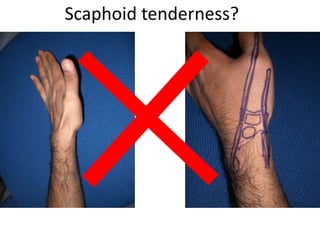

- Naming the bones, joints, tendons, nerves and skin landmarks of the hand and wrist.